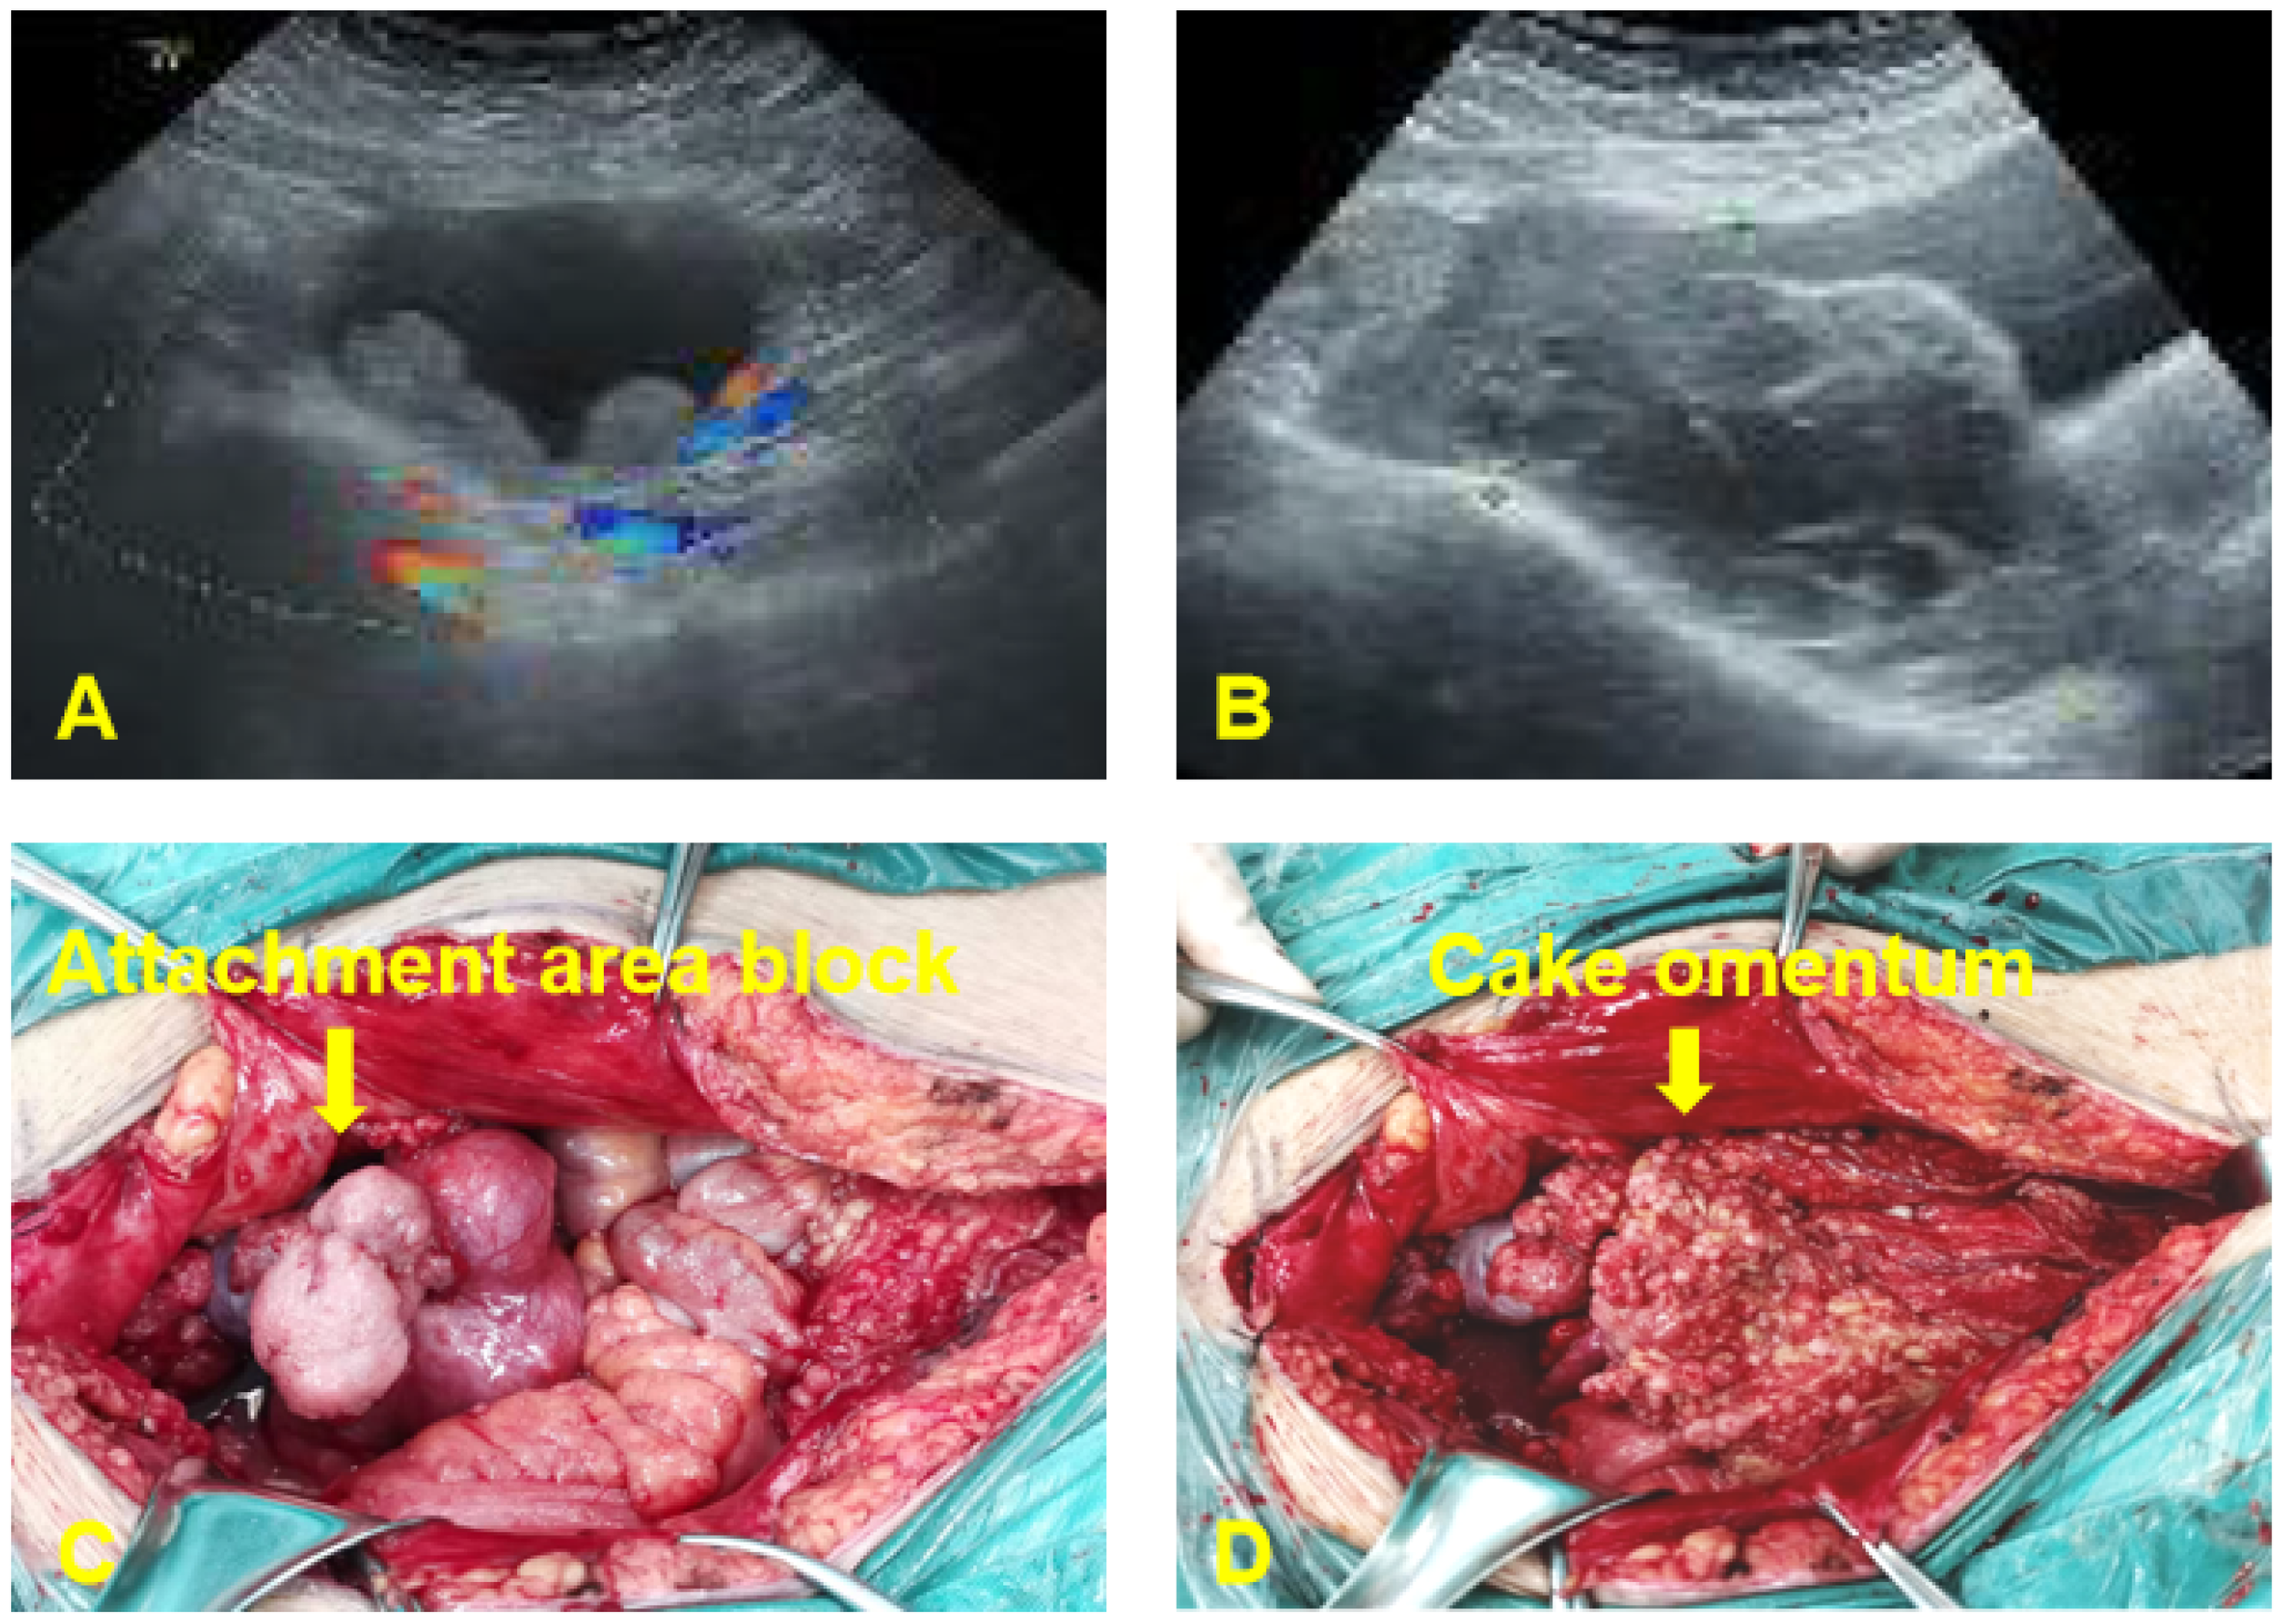

One year after surgery, due to sudden abdominal distension, the patient underwent a whole abdomen CT, which revealed multiple malignant tumors in the pelvis, indicating extensive metastasis to retroperitoneal lymph nodes, peritoneum, and greater omentum. A chest CT revealed enlarged lymph nodes in the right cardiophrenic angle area, with potential metastasis; the tumor was considered to be recurrent with malignant changes. Tumor marker levels were elevated CA125(453.9 U/mL). On May 10, 2022, an open laparotomy was performed. During the operation, approximately 4000 mL of reddish ascites was seen in the pelvis. The size of the uterine corpus was normal with scattered granular nodules on the surface. An exophytic granular mass approximately 12 cm in diameter was seen in the right adnexal area, and an 8 cm diameter mass in the left adnexal area, with histological structures that were difficult to recognize and no typical tubal-ovarian tissues detected. Furthermore, a 6 cm diameter granular mass was detected in the uterine rectal sulcus. The peritoneum of the uterine rectal recess and the bladder and uterus exhibited nodular thickening. The greater omentum was markedly thickened with granular nodules scattered across its surface. The omentum of the splenic region was markedly thickened, and 2 cm metastatic nodules were seen at the lower level of the spleen. The appendix was markedly thickened, with granular nodules visible on its surface. Furthermore, granular nodules were observed throughout the pelvic and abdominal peritoneum, at the diaphragmatic apex, in the hepatic and renal crypts, along the hepatic ligament, the perihepatic peritoneum, the perisplenic peritoneum, the small bowel, the colon, and mesenteric membrane, ranging 0.2-3 cm in diameter. Granular nodules, most of which were loosely attached to the metastatic site, and enlarged lymph nodes of approximately 5 × 4 cm in size were found on the left side of the abdominal aorta and below the renal vessels, which were fixed, and no obvious enlargement of the pelvic lymph nodes was detected as shown in Figure 1. During intraoperative cryopathology, neoplastic lesions were identified both in the left and right adnexa. These lesions exhibited morphology similar to the previously diagnosed left tubal mesenchymal tumors but with increased heterogeneity and prominent nuclear fission. The opinion was malignant, and female adnexal tumors of mesonephric (Wolffian duct) origin or gonadal-mesenchymal tumors (with malignant biological behavior) were considered. Since the patient was infertile, after explaining her condition to her family, she underwent tumor cytoreductive surgery (R1). This included bilateral adnexectomy, total extrafascial hysterectomy, lymph node dissection (pelvic, para-abdominal aorta, presacral), resection of pelvic metastases, omentectomy, appendectomy, and hyperthermic perfusion chemotherapy for cancer. The postoperative pathological examination revealed the following findings: (1) (Bilateral) ovarian neoplastic lesions with microscopic tumor cells arranged in sieve-like, reticulum-like, solid sheets or tubules, with heterogeneous cells, prominent nuclei, and easily visible nuclear schizophrenic images, suggesting a diagnosis of Wolffian duct tumors. (2) Tumor infiltration was identified in intestinal surface nodules, pelvic masses, pelvic peritoneum, appendix, and greater omentum. (3) Lymph node metastases were detected below the renal artery and in the para-aortic region (2 out of 2 lymph nodes). Immunohistochemistry results revealed the following: CKpan (+), Vimentin (partially +), ER (++, about 30%), PR (++, about 15%), Calretinin (+), Inhibin α (a small amount of +), CD10 (+), β-Catenin (membrane +), and Ki-67 (+, 40%) as shown in Figure 2. The final diagnosis was a malignant tumor of the fallopian tube (stage IV).

Figure 1

Preoperative ultrasound examination and intraoperative investigation of the patient. (A) Lunar 4, 2021: A 7.0*7.6 cm cystic mass was found in the upper left part of the uterus, with a thick cyst wall and multiple slightly hyperechoic protrusions. (B) May 10, 2022: A 12.8x10.1x5.8 cm solid cystic mass with a detached and multilocular cystic portion was present in the right adnexal region. The mass crosses the anterior aspect of the uterus and involves the left ovary. (C) Exophytic granular masses in the adnexal region bilaterally. (D) Granular metastatic nodules in the greater omentum.